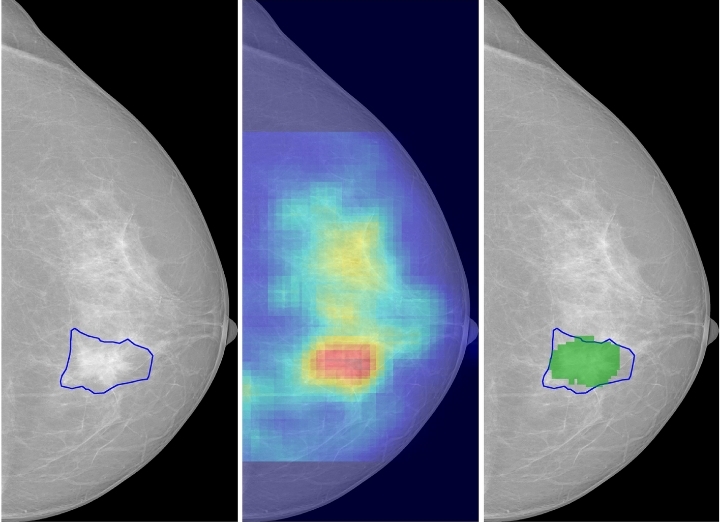

Consider side-by-side mammograms from MIT research: an early scan might look “normal” to a doctor, but the AI flags a faint irregularity (highlighted in red). Years later, that same area reveals a tumor. Saliency maps—heatmaps generated by the AI—highlight exactly where the model sees risk, providing radiologists with explainable insights.

Saliency of breast lesions in breast cancer detection using artificial intelligence. Image Source – Scientific Reports

International validation adds credibility. Mirai performed consistently across diverse populations in Sweden, Taiwan, and beyond—crucial for global equity. A 2024 study in the Journal of the National Cancer Institute demonstrated AI could flag interval cancers (those appearing between screenings) up to 30% earlier, potentially reducing advanced diagnoses.

Even commercial tools not originally designed for long-term prediction, like Transpara, showed strong associations with invasive cancers 2–5.5 years later. The AI’s discriminatory power often matches or exceeds established models, and it’s particularly effective for dense breasts—a known challenge in mammography.